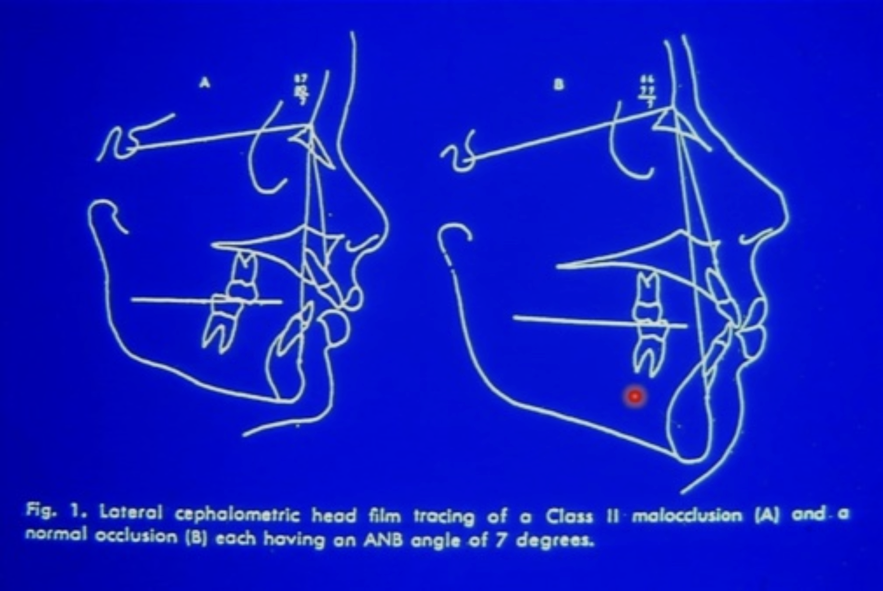

Wits Analysis

ANB 沒意義: 受 N 點前後位置影響

看 A, B 到 Oc 垂足距離

- AO-BO 平均值男性為1 mm、女性為0 mm